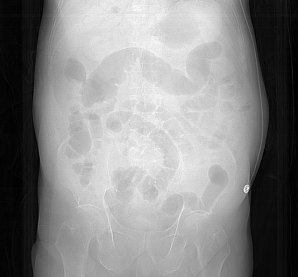

腹胀明显,肠道积气